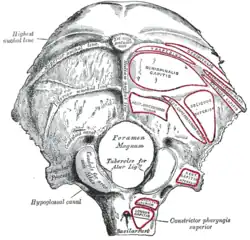

Posterior view of neck bones (rectus capitis lateralis muscle shown in red) | |

The rectus capitis lateralis, a short, flat muscle, arises from the upper surface of the transverse process of the atlas, and is inserted into the under surface of the jugular process of the occipital bone.